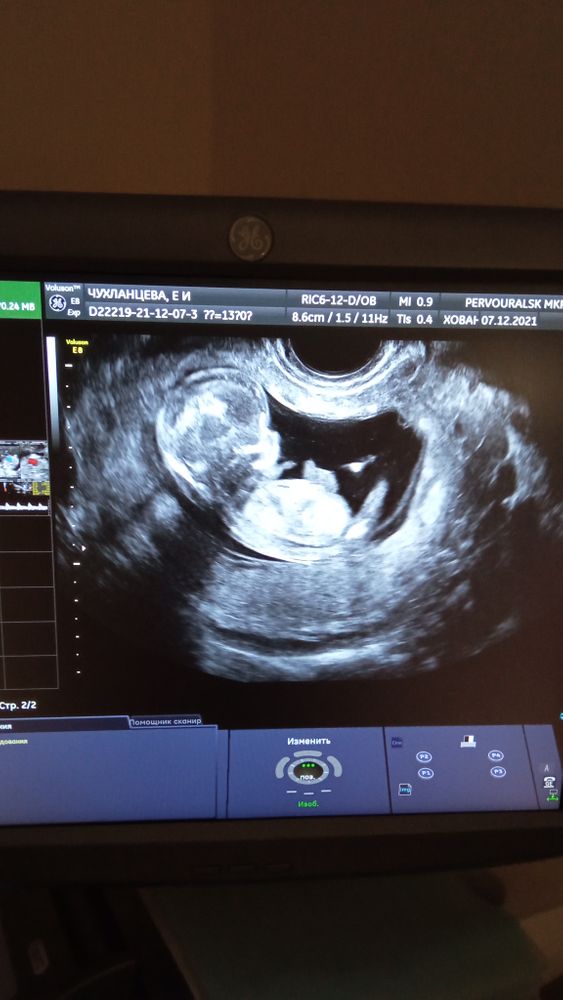

Первый Скрин💕

Вчера была на первом скрине (13 недель) и увидела своего малыша😍 какой он маленький и миленький☺☺☺ конечно пол нам пока что не сказали, нот главное чтобы был здоровый❤ мы тебя очень любим и ждём наш малыш ❤ твои мама, папа и сестрёнка 🙏😘